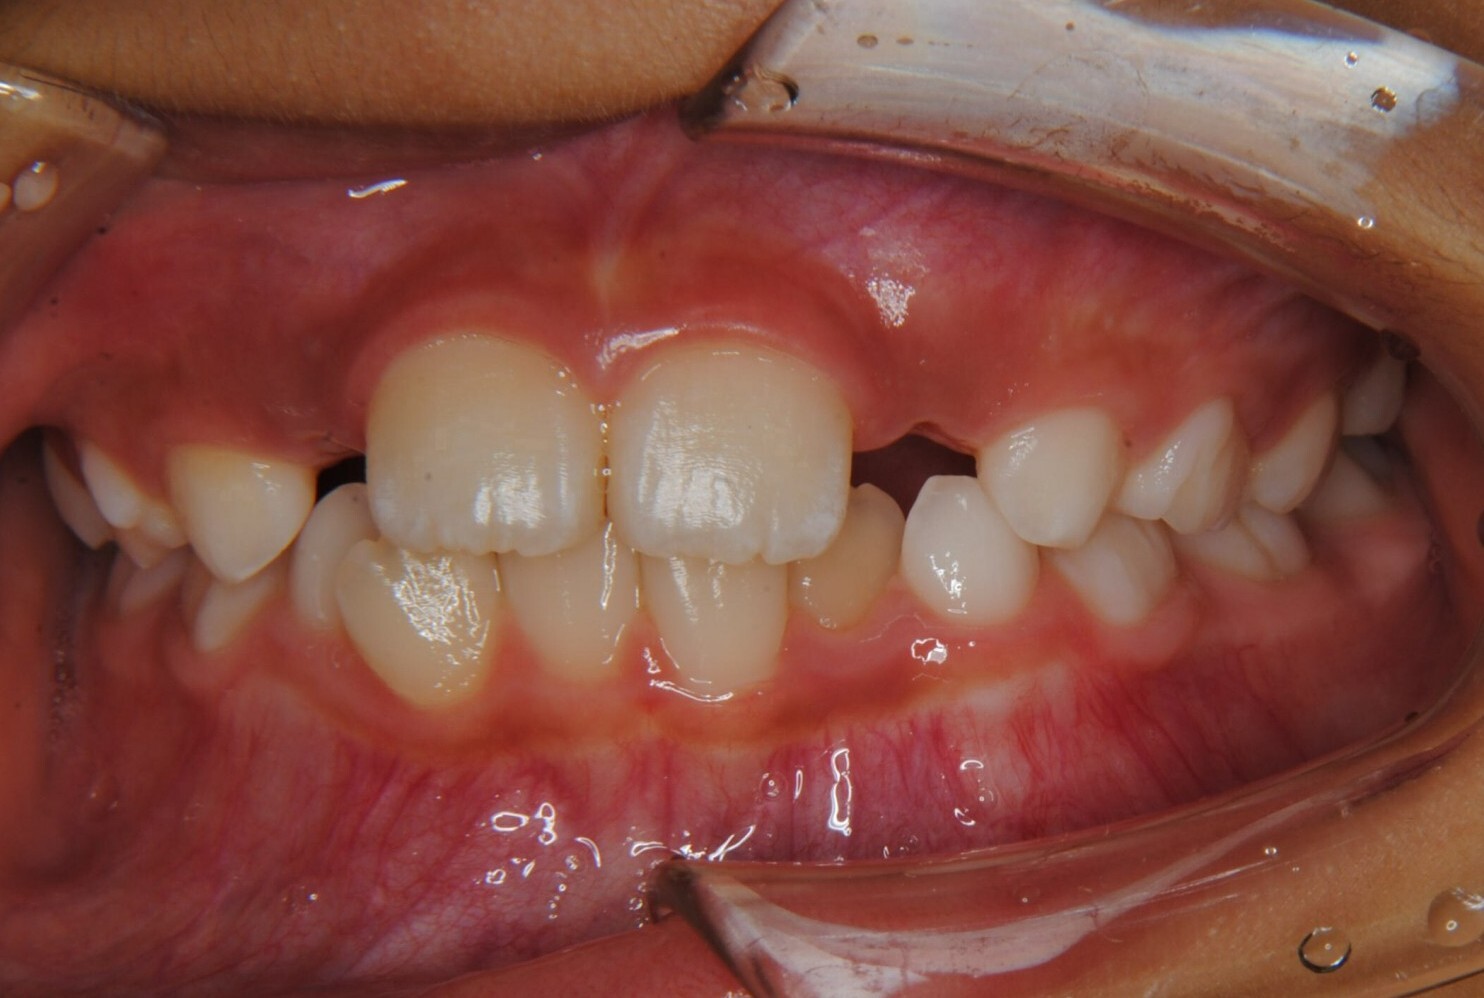

①主訴:下の前歯のデコボコ

②診断名:Ⅰ級叢生

③年齢:初診時(左写真)8歳6か月、終了時(右写真)11歳4か月